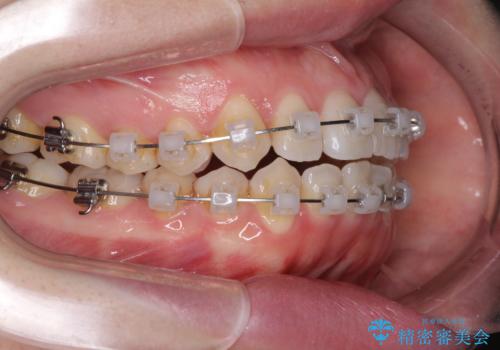

前歯のデコボコを治したい ワイヤー矯正

- クリアブラケット

- 前歯のデコボコが気になるとのことで来院された患者様です。

目立たない装置と金属のワイヤーで矯正治療を行うこととしました。

1年半程度の期間を見込んでいましたが、上下の真ん中の位置をできる限り合わせるための調整に少し時間がかかってしまいました。

咬み合わせが安定し、前歯の汚れも付きにくくなりました。